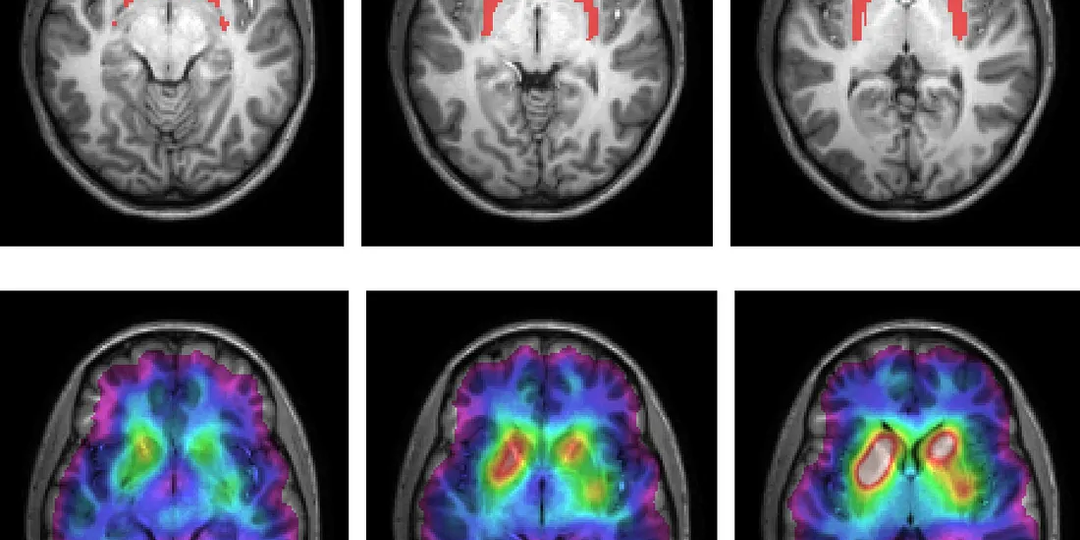

Как нейробиолог, я отказался от этих 5 утренних привычек, которые разрушают ваш мозг

Ваше утро — это уникальная возможность максимально усилить работу мозга на весь оставшийся день. То, что вы делаете (или не делаете) в первые 60–90 минут после пробуждения, влияет на ваше настроение и когнитивную продуктивность в течение следующих часов. Но болезненная правда в том, что большинство людей сами того не осознавая вредят своему мозгу ещё до 9 утра, а потом удивляются, почему им трудно сосредоточиться или почему они постоянно испытывают стресс. Следующие пять утренних привычек очень распространены, и в прошлом я сам тоже им следовал. Давайте разберём их с точки зрения нейробиологии и рассмотрим более удачные альтернативы для каждой из них. Эта привычка чрезвычайно распространена. 84% населения США проверяют телефон в течение первых 10 минут после пробуждения: Почему это проблема: В первые 30–45 минут после пробуждения происходит так называемая реакция кортизола при пробуждении (Cortisol Awakening Response). Это резкое повышение уровня кортизола утром. Здоровая реакция корти